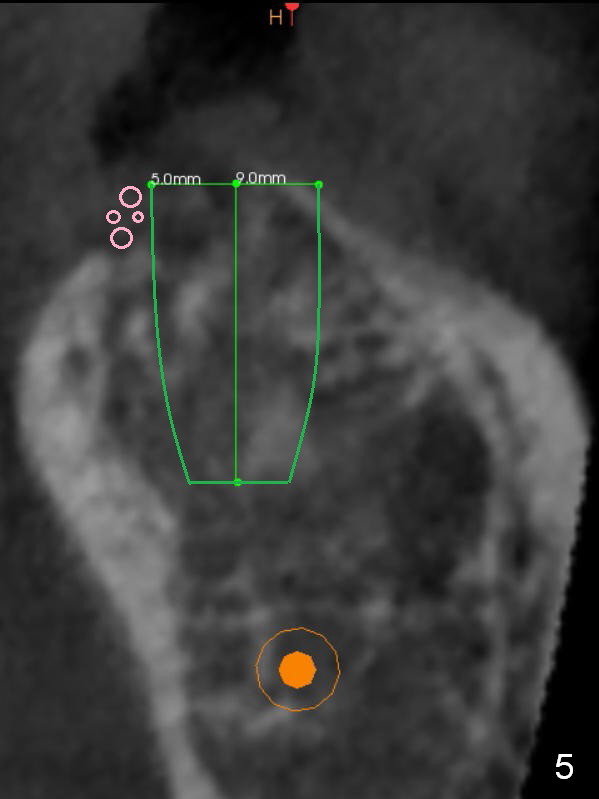

Preop palpation of the edentulous area at #18 does not show the flatness of the ridge top as shown by CBCT. Incision reveals that the ridge is not as wide as CBCT indicates (Fig.1 (coronal section) between arrowheads). In fact the ridge is concave (Fig.2 red dashed line). Osteotomy is initiated in the middle of the concavity (Fig.2 green line) with insertion of 7 mm guide pin (Fig.3). After removal of the pin, the osteotomy is moved buccally (Fig.4). After Marking Bur and 4.3 mm Magic Drill, a 5x9 mm IBS implant is placed with 2.8 mm clearance from the Inferior Alveolar Canal (Fig.6). Following deepening the osteotomy with Final Drill, the implant is placed deeper (Fig.7). The osteotomy happens to be established in the mesial socket, since the distal socket has not completely healed (Fig.6 yellow dashed line). Granulation tissue is removed. Since the lingual crest is lower than the buccal one (Fig.1 B), there is lingual thread exposure after implant placement (Fig.5). The exposed thread is covered by bone graft (autogenous bone, allograft and Osteogen, Fig.5 pink circles). Some of the graft is apparently pushed into the distal socket (Fig.7 yellow dashed line) post GBR and suture. As the implant is placed twice, insertion torque is <10 Ncm (although the implant is stable). A 5x3 mm healing abutment is placed (Fig.7 H).